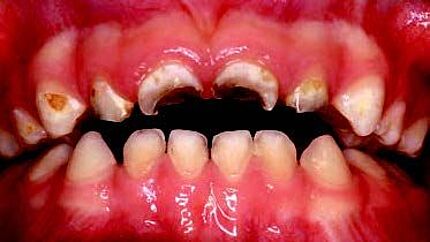

Ein 34-jähriger Patient hatte die häusliche Mundhygiene ohne erkennbare Gründe fast vollkommen eingestellt. Die daraus resultierende desolate orale Gesamtsituation war mit seinem äußeren Erscheinungsbild und seinem sozialen Status nicht vereinbar. Aufgrund dieser Widersprüche erfolgte eine intensive Abwägung der Therapieoptionen.

Zeitschrift: ZM – Zahnärztliche Mitteilungen

Ausgabe: 21/2019, Seiten 46 – 50

Freigabe zur Veröffentlichung erteilt durch den Deutschen Ärzteverlag

Autoren: PD Dr. Michael Korsch, M.A., Dr. Abdel-Karim Mamar